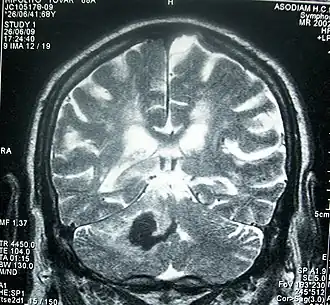

RMN de cráneo que muestra una hemorragia intracerebral profunda (cerebelo): zona oscura, 30 horas desde el inicio de la enfermedad actual. | ||